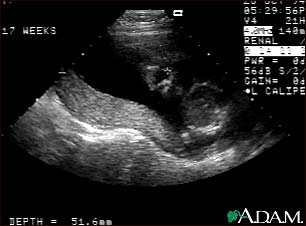

Ultrasound, normal relaxed placenta

This is a normal fetal ultrasound performed at 19 weeks gestation. This ultrasound shows two interesting features. In the foreground, to the left and middle of the screen, you can see the placenta, following the curve of the uterus. In the background on the right, where the cross hair is pointing, you can see the face with all the facial features visible.